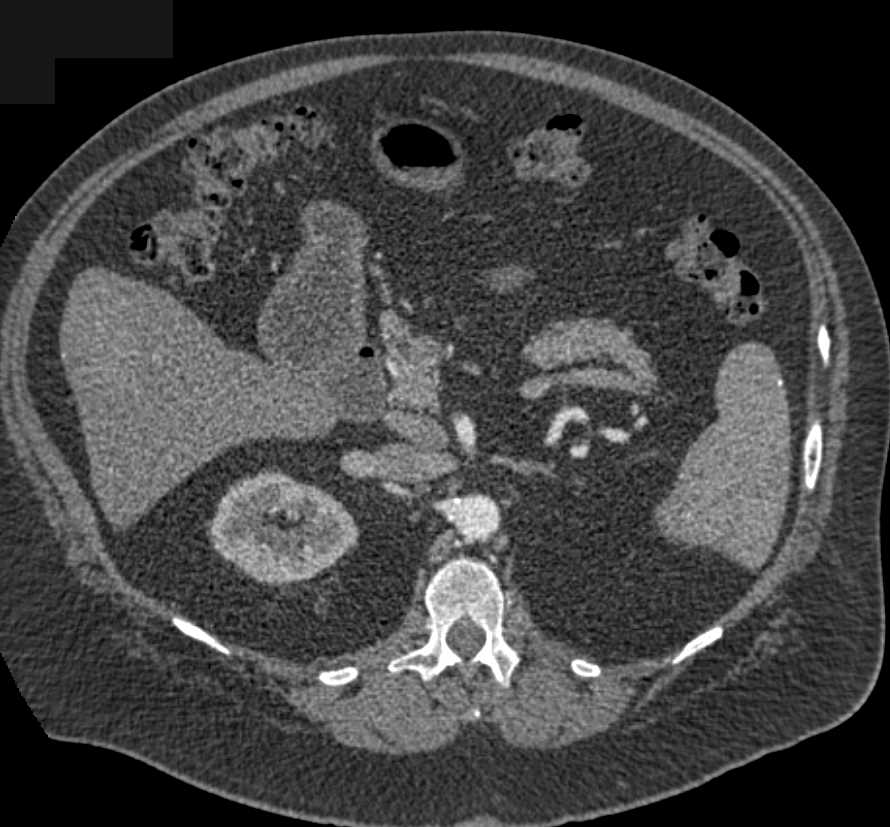

Clear Cell Renal Cell Carcinoma (ccRCC) Invades Left Renal Vein and Inferior Vena Cava (IVC)